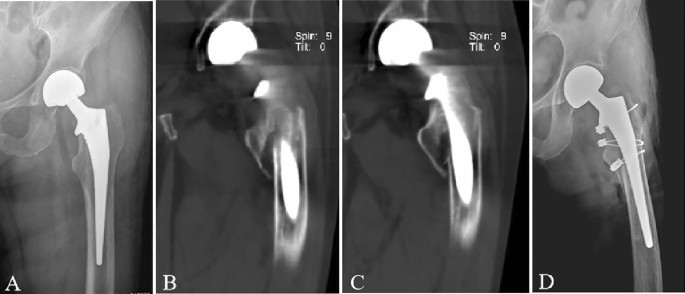

Two treatment methods were adopted. Longer stem revision and internal fixation (LSRIF) with cables was applied in 24 cases (Figs. 1 and 2). Open reduction and internal fixation (ORIF) with cables was done in four cases (Fig. 3). The choice of surgical treatment was based on the patient’s physical condition. The standard treatment was LSRIF, while ORIF was chosen if the patient was in poor condition and could not tolerate LSRIF.

Postoperative pseudo ALT fractures were seen in 28 patients (7 males [25% and 21 females [75%]). The age of the patients at surgery was 73.7 (range: 52–92) years. Of the cases, 27 (96.43%) occurred with non-cemented stems, and 1 (3.57%) with cemented stems (Fig. 4). The basic patient data are summarised in Table 1.